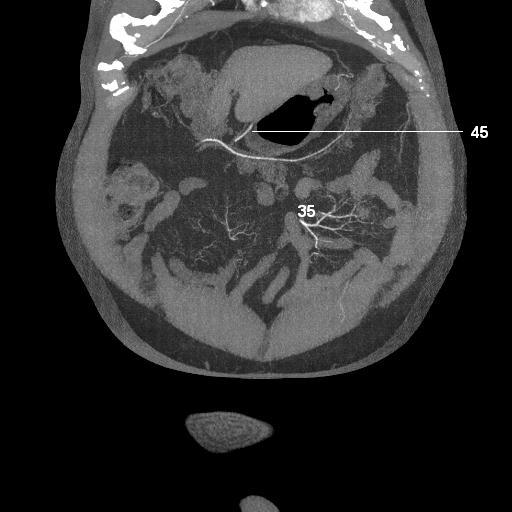

35. jejunal arteries

45. right gastroepiploic artery